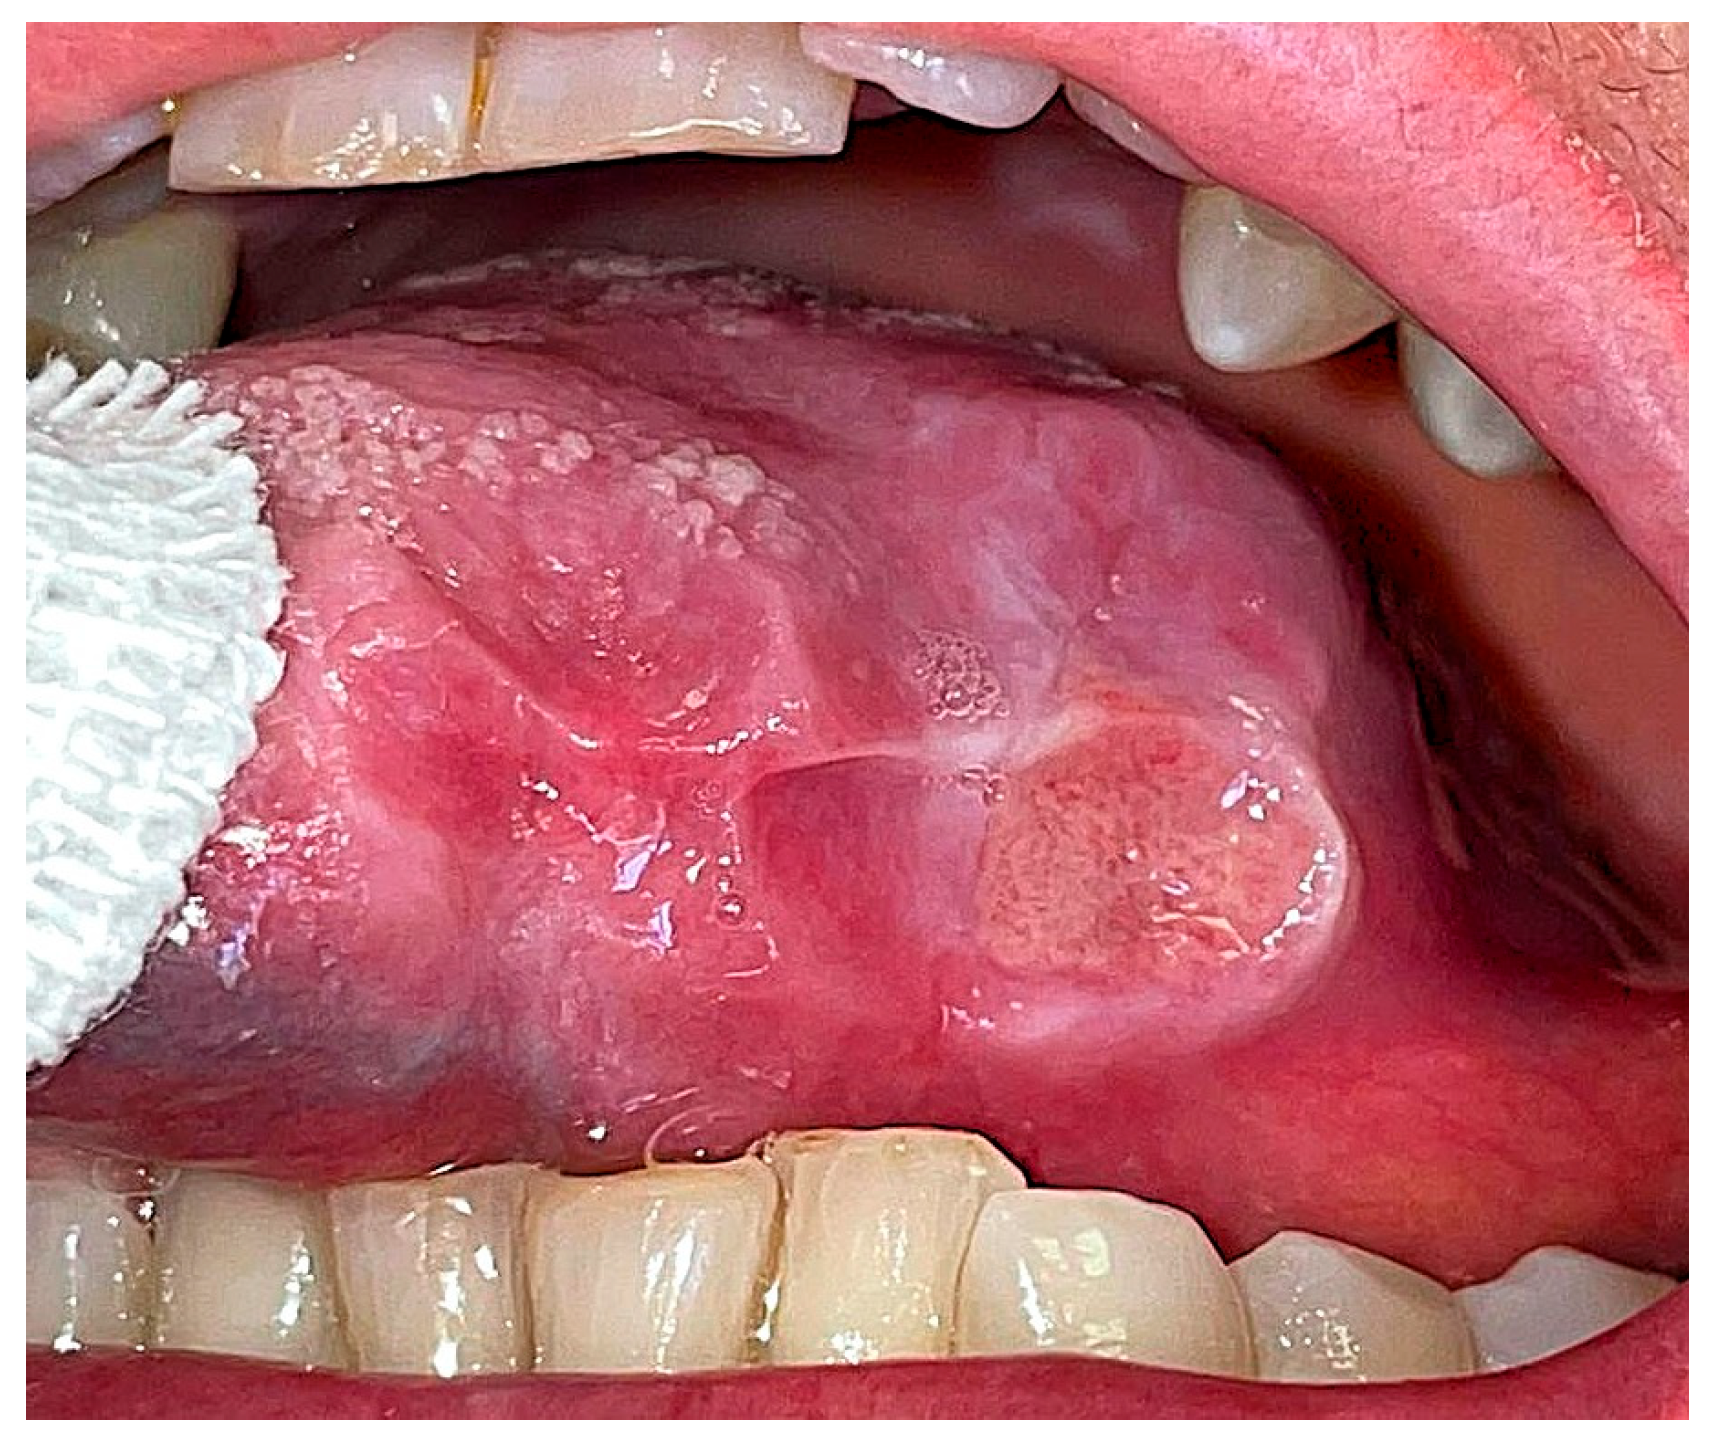

Case Treatment

3. Results